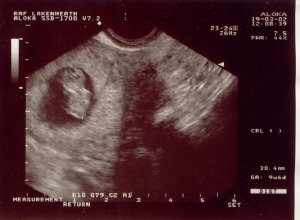

My Latest Ultrasound.... I just had an ultrasound on Tuesday, July 11th. I was so excited that all ate that morning was a Chewy Granola Bar. The ultrasound was at 1:00 p.m., so during the ultrasound, I almost fainted. The room started to go black. My body temperature felt like it was dropping, BUT I broke out in a sweat, and the sound drained from the room. All I could do was grab Duane's hand, as if holding on for my dear life. Go figure. Can anybody say "low blood sugar." Oh well. My husband gave me the whole lecture on how breakfast is the most important meal of the day, etc.... So you can all save your preaching for another day, thank you very much. Other than that, the whole day was so exciting! WE'RE HAVING A BOY! Here are some ultrasound pictures for you. Sorry they're not that clear but it's better than nothing, right? Enjoy...

Here are some Ultrasound Pictures we took when the baby was only 8 weeks old...